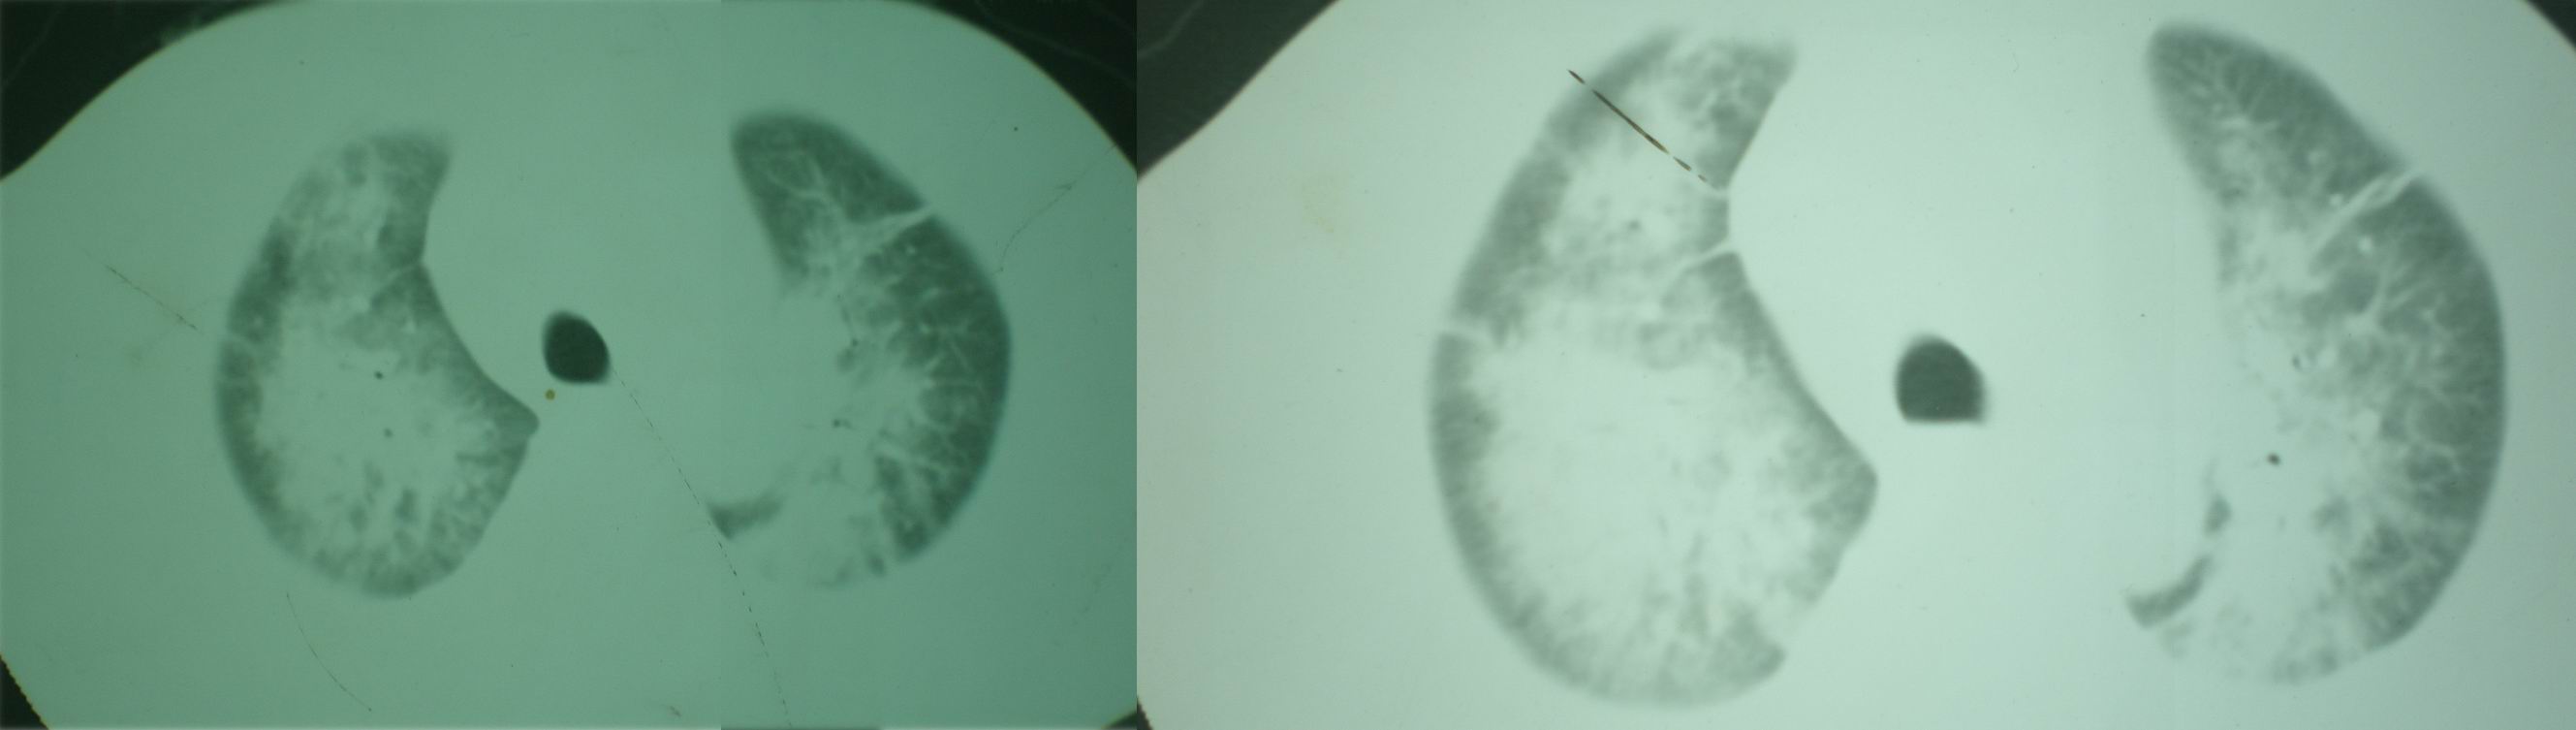

病人资料:男,52岁,因体癣股癣等皮肤病行激素治疗,因突然大剂量减药而起病,病情危急,9月8日曾在上级医院住院治疗,9月18日复查了ct片,相关检查及住院小结以图片资料上传。

2008年9月8日ct片:

机遇性感染!不除外急性肺水肿!

急性心衰所致肺水肿,双侧胸腔积液,少量心包积液可能?结合临床及其它检查.

我仔细看了下病人的出院小结,当时情况危急,诊断里有1型呼衰。心包周围的是脂肪密度。结合三次ct扫描的图象分析,个人认为:1、病人目前肺部病灶基本消失,双侧胸腔内少量积液,抗结核治疗才一个多月,就算是结核,抗结核治疗有效果,为何效果如此好,一点纤维灶的痕迹都没有呢,再就是患者做过气管镜检查及活检、痰检均未找到结核的证据。所以不支持结核的诊断。

急性呼吸窘迫综合征,肺水肿,与激素减量太快有关.双侧胸腔积液.

机遇性感染。双肺实质满布。且以肺门周围为主。不象结核。